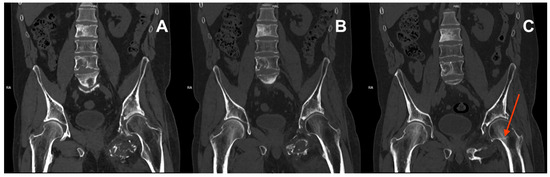

Upon presentation in August 2023, a CT scan revealed a subcapital fracture of the left femoral neck in the healing phase (Figure 3). The retrospective reassessment of the previous CT performed in April 2023 demonstrated an early stage of femoral neck fracture at the border of the examination range. There was no history of trauma and only mild exacerbation of pain during weight bearing. After consultation with an orthopaedic surgeon, the treatment was abandoned due to the presence of cancer-related changes in the pelvis, the stable nature of the fracture, and the patient’s compromised mobility, which allowed him to function despite the unnoticed fracture. Furthermore, surgery would likely involve significant challenges, including a questionable prognosis for successful healing. The second course of palliative RTH on the pelvis area (30 Gy in 10 fractions) was administered in April 2024. Currently (Figure 4), the patient is continuing therapy with sirolimus and pamidronate, remaining professionally active (November 2024).

Figure 3. CT scans from September 2022 (A), January 2023 (B), and April 2023 showing decreased bone density in the left femur and pathological lesions in the vertebrae and left pelvic bones. Early signs of a subcapital fracture of the left femoral neck (red arrow) first seen in the CT from April 2023 (C).

Figure 4. CT scan from August 2023 (A) showing extensive lytic infiltration of the left ischium at the initial tumour site (red arrow). Coronal plane maximum intensity projection (MIP) of the same CT (B). Impacted fracture of the left femoral neck (blue arrowhead) caused by the neoplastic infiltration. Pathological lesions in the left ischium and hip bone as well as in ribs 10 and 11 on the right side.